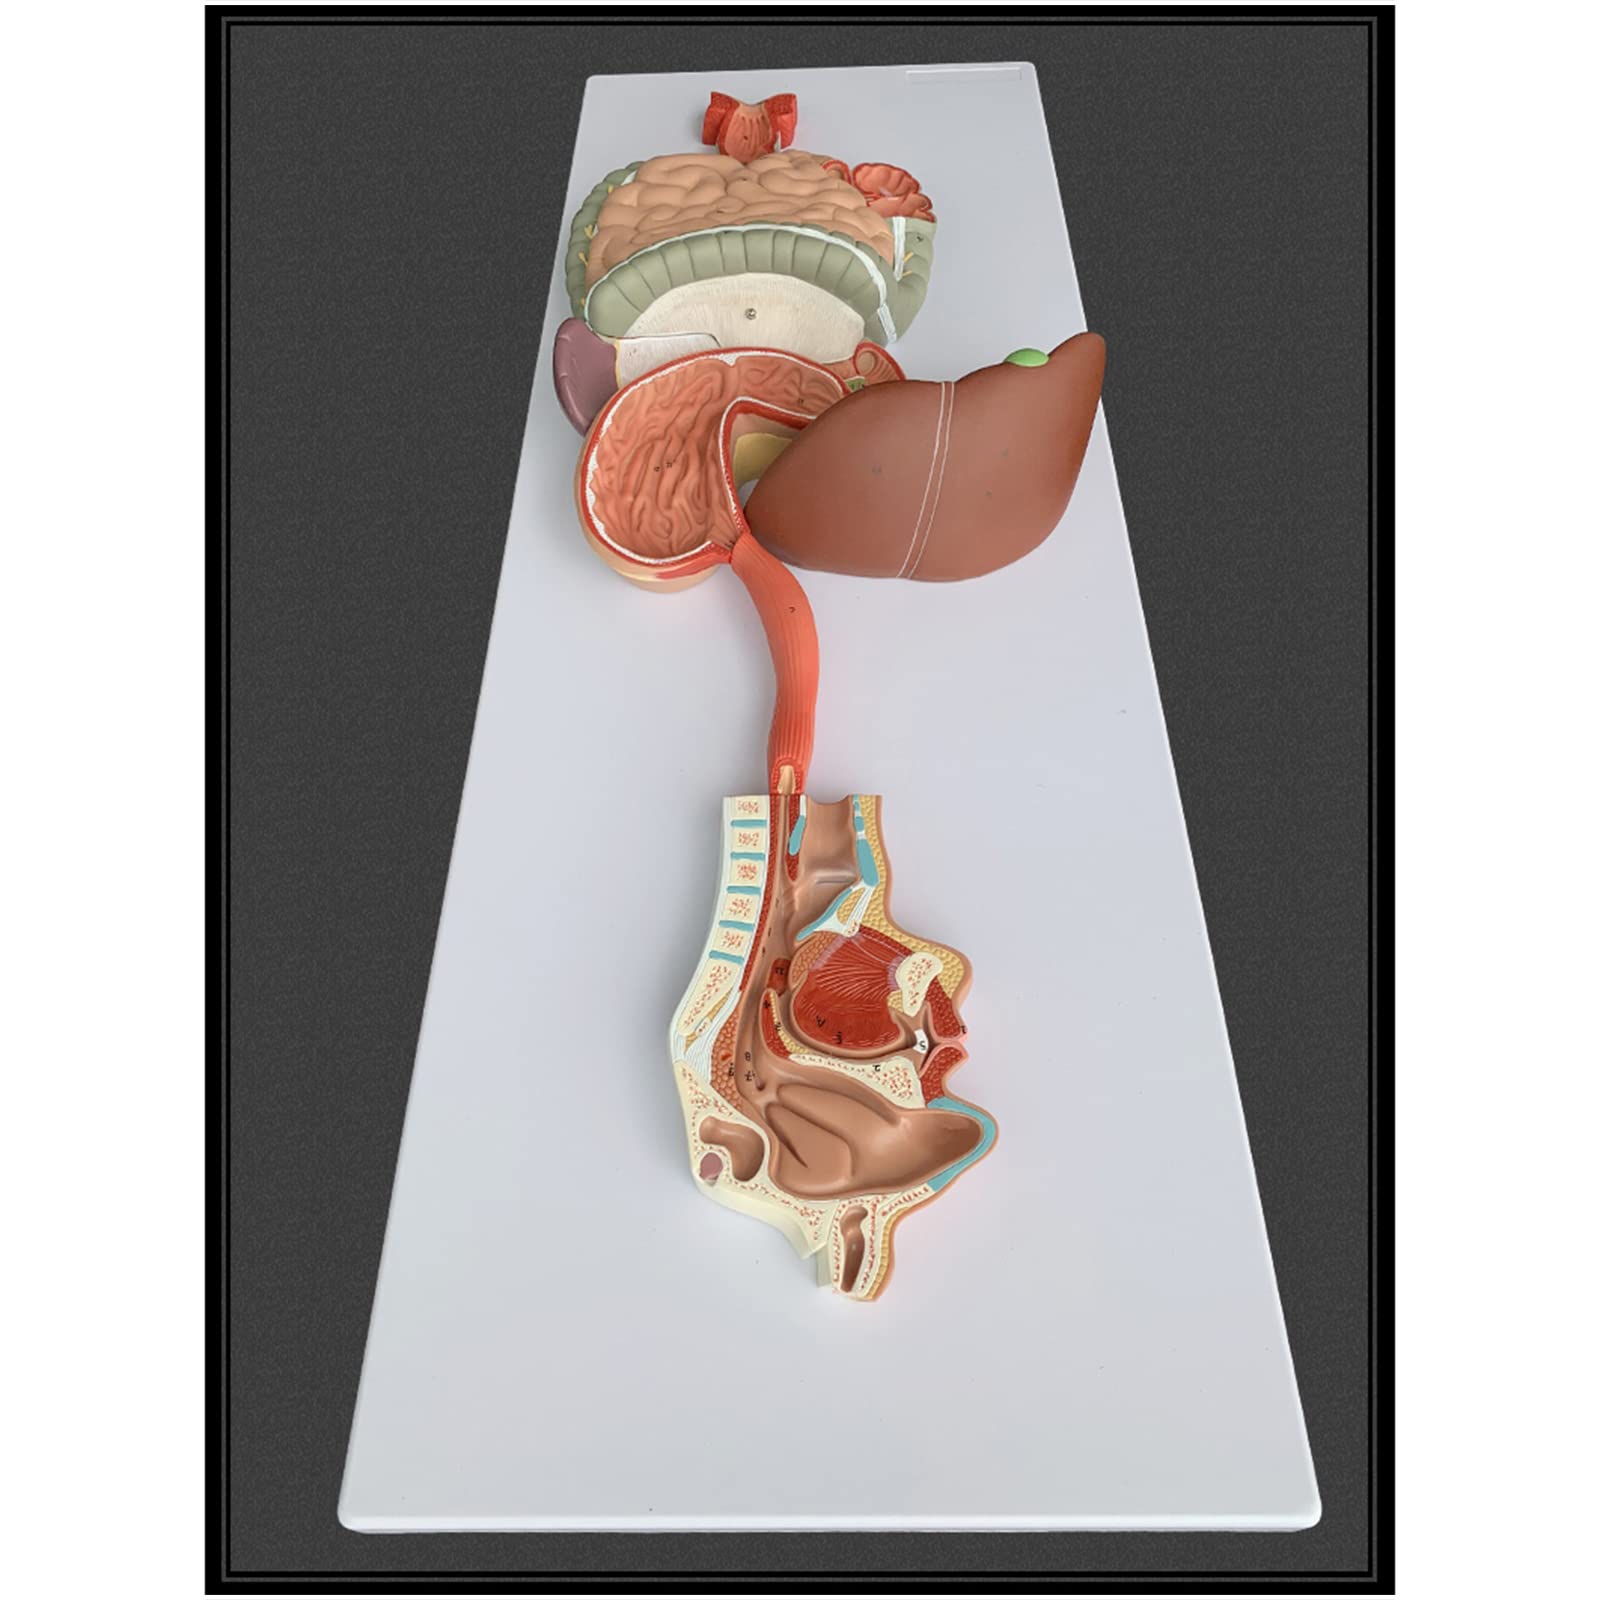

- INTERACTIVE LEARNING EXPERIENCE - Disassemble and explore the digestive system like never before!

The Human Digestive System Model is a life-size, three-dimensional representation of the human digestive tract, designed for educational purposes. It features disassemblable parts for interactive learning and is made from durable, anti-corrosive PVC material, making it an essential tool for anatomy students, educators, and healthcare professionals.